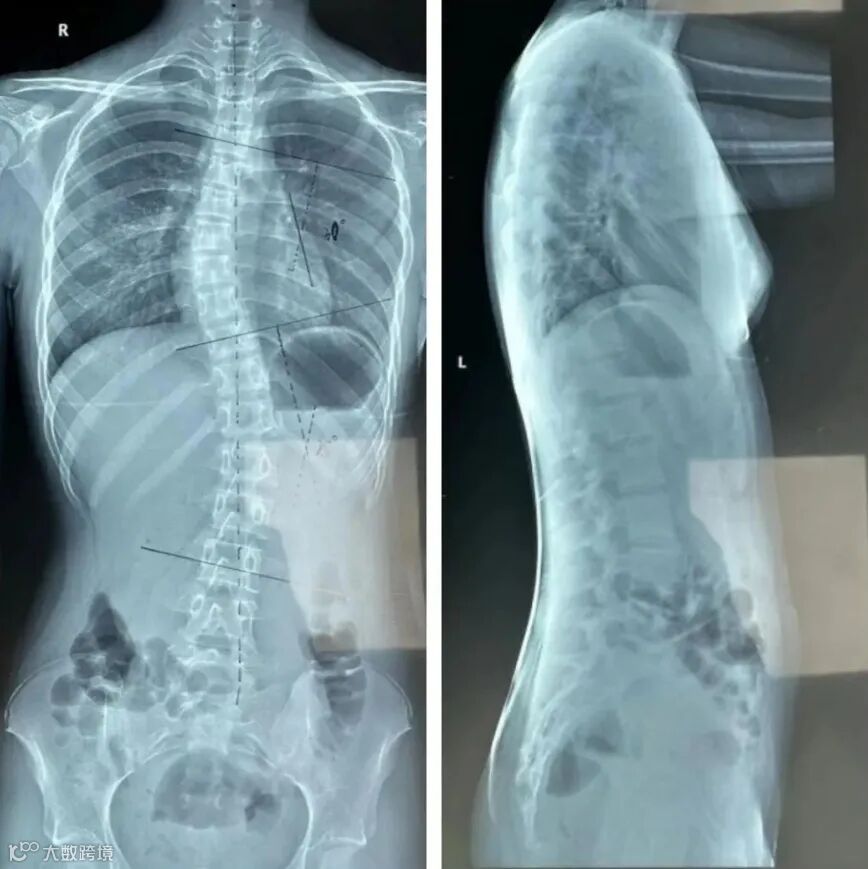

王同学,女,11岁,6年级,在一次学校的集体筛查中发现双肩不等高,Adam实验剃刀背明显,家长带孩子随向医院拍片发现脊柱侧弯,穿戴前首次制作支具前评估:胸段Cobb角37°,腰段Cobb角21°,椎体旋转度Ⅲ度,Risser症Ⅲ度,月经来潮1年,高低肩明显。

穿上支具经过一周适应期后复查:胸段Cobb角12°,腰段Cobb角10°以内,(因颈椎段侧凸位置较高矫正受限)由于孩子家长比较重视且孩子配合度比较高每天穿戴20小时以上,矫正效果明显。

穿戴前 穿戴后